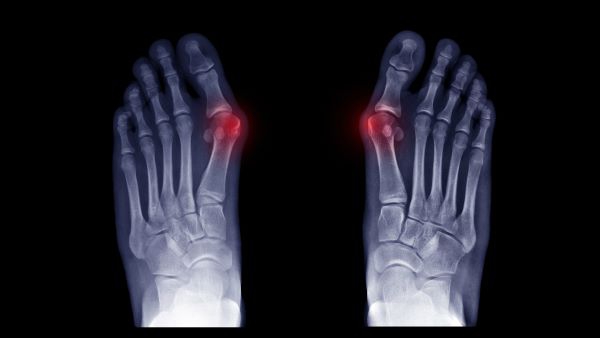

X-ray and UltrasoundX-ray and Ultrasound

When foot pain threatens to disrupt your busy schedule, getting an accurate diagnosis and effective treatment shouldn’t add to your stress. Don’t wait days or weeks for the diagnostic imaging and care you need to get back on your feet. At Foot & Ankle Concepts, our board-certified Southern California podiatrists offer same-day, on-site X-rays and ultrasounds at convenient locations in Ventura County, Los Angeles County, and Santa Barbara County. Receive an evaluation, diagnosis, and personalized plan to help you recover and return to your active lifestyle.

MIS BunionMIS Bunion

If a painful bunion is limiting your ability to wear your favorite shoes or enjoy everyday activities, minimally invasive bunion surgery might offer the relief you've been seeking. At Foot & Ankle Concepts, our experienced Southern California podiatrists specialize in advanced MIS bunion procedures that provide excellent outcomes with smaller incisions, reduced discomfort, and shorter recovery times compared to traditional bunion surgery.